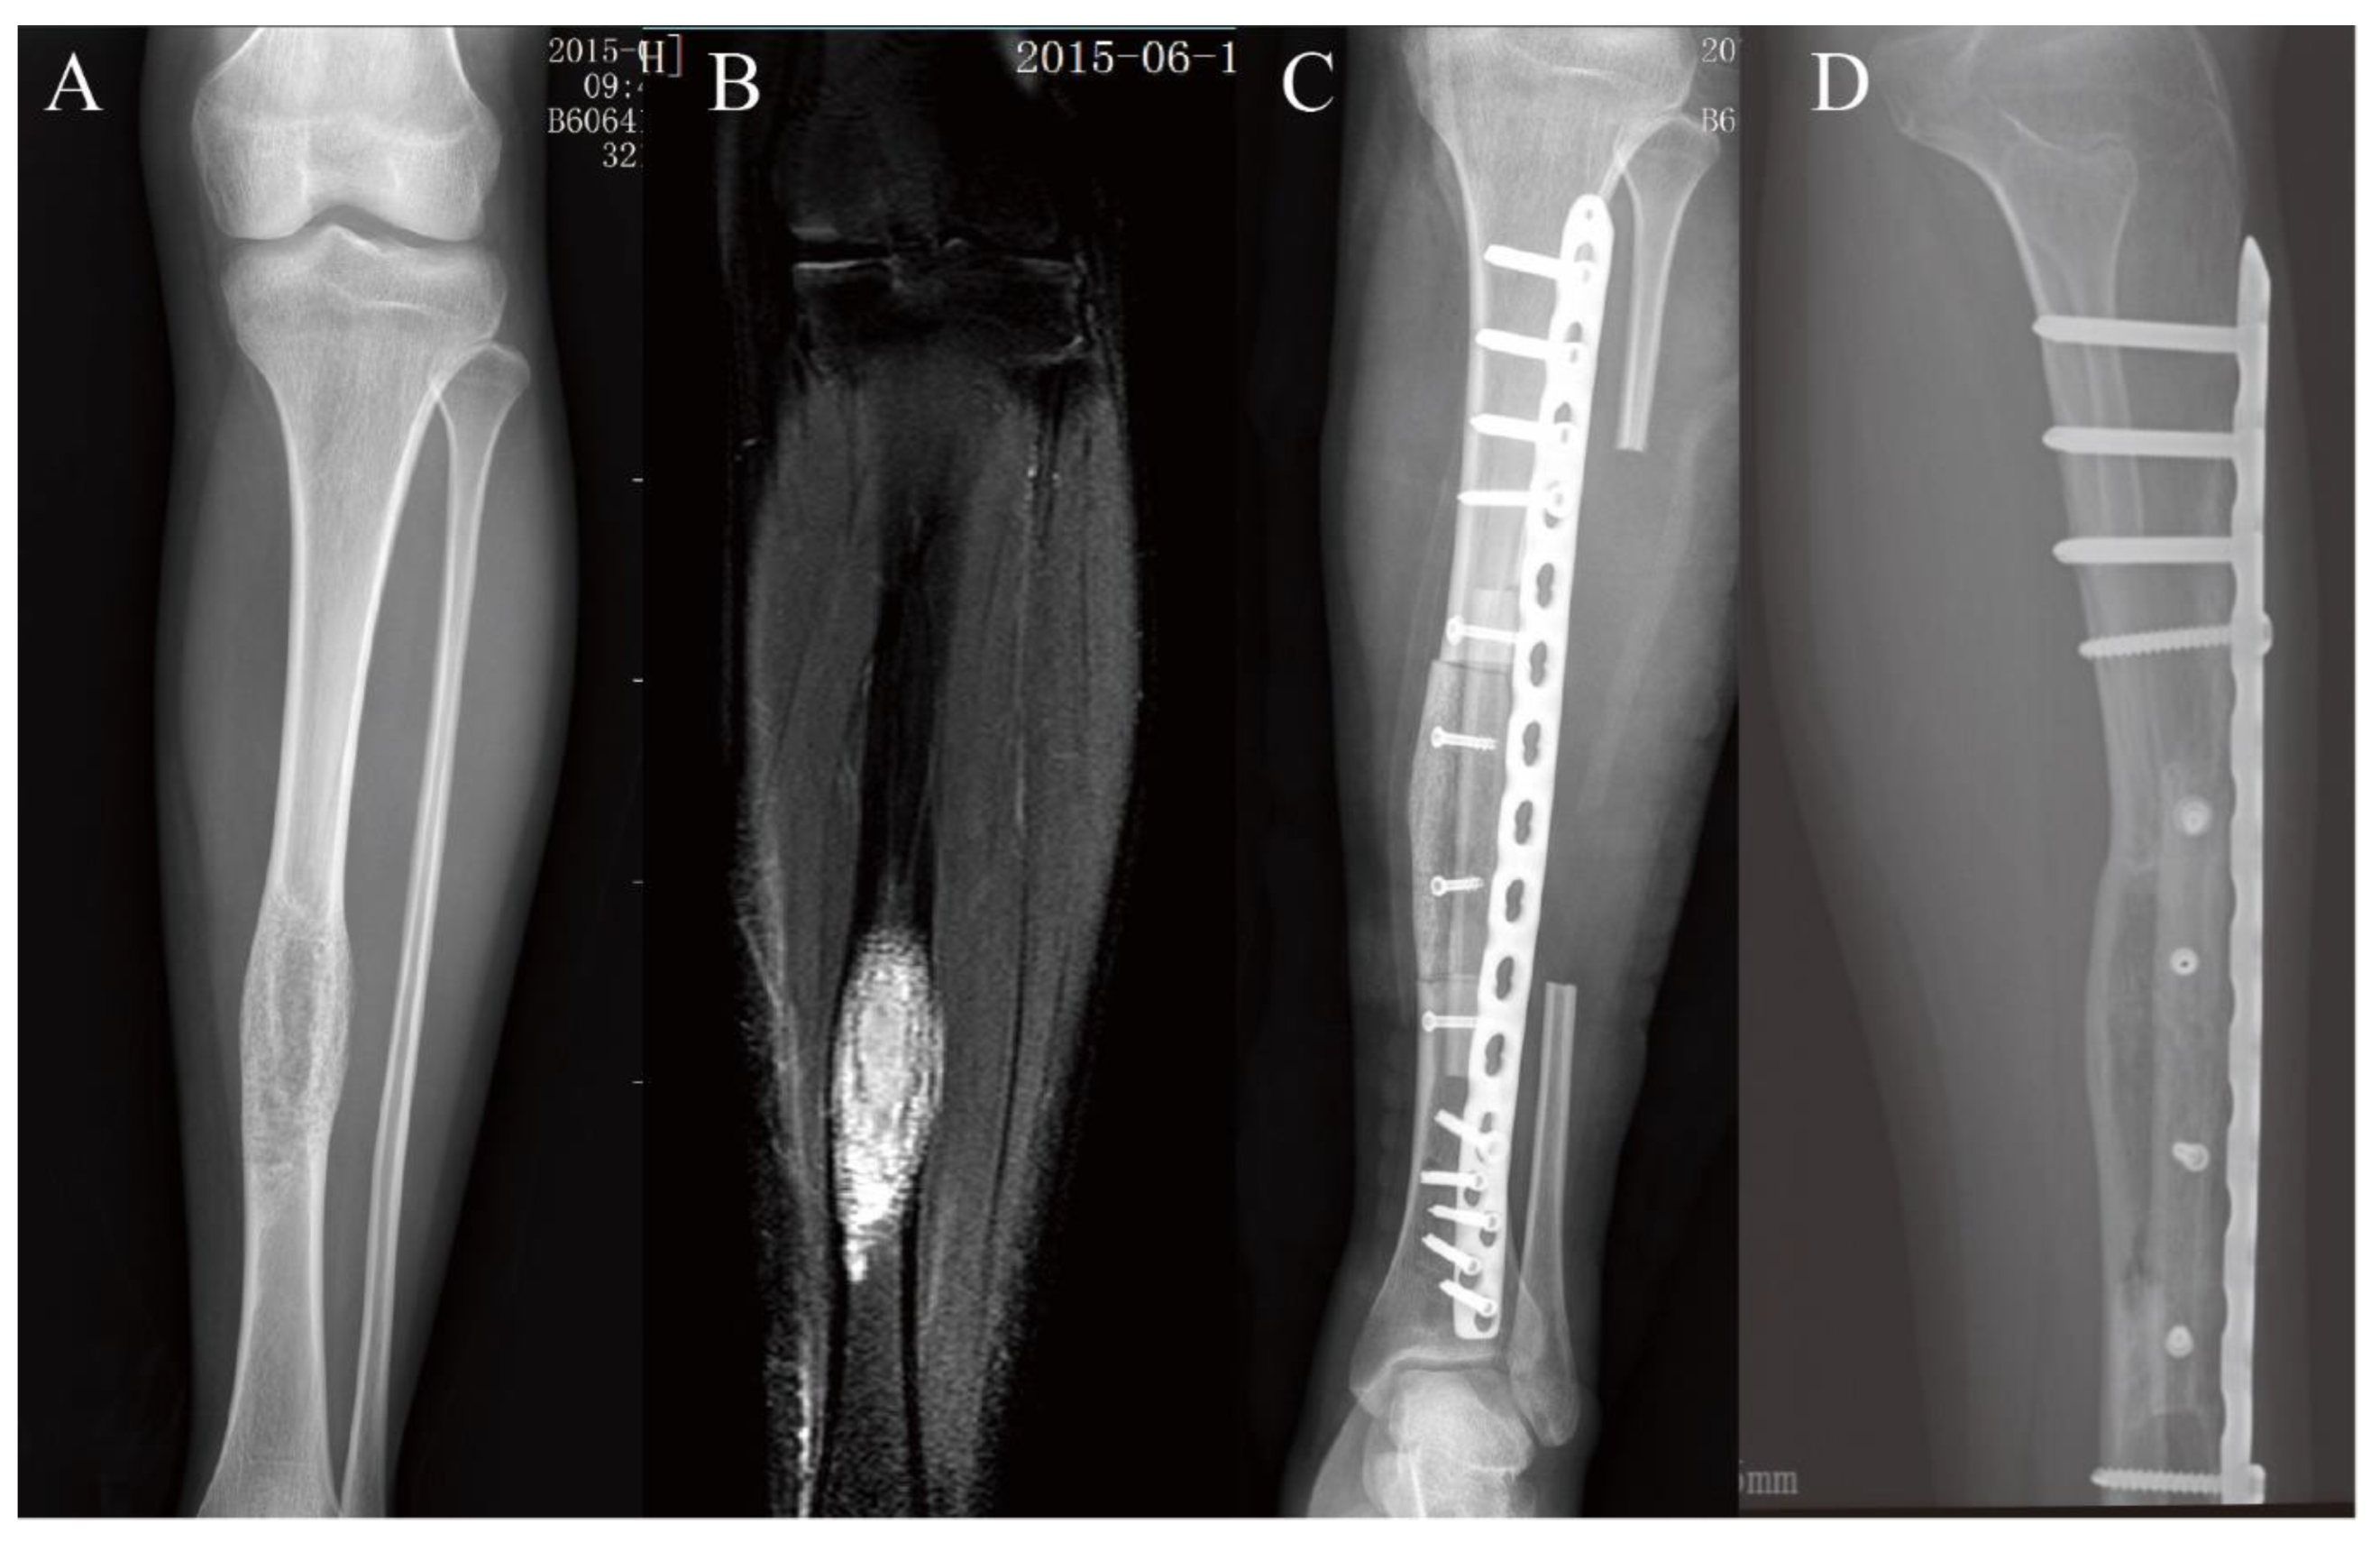

3.2. Lower Extremity Reconstruction Results